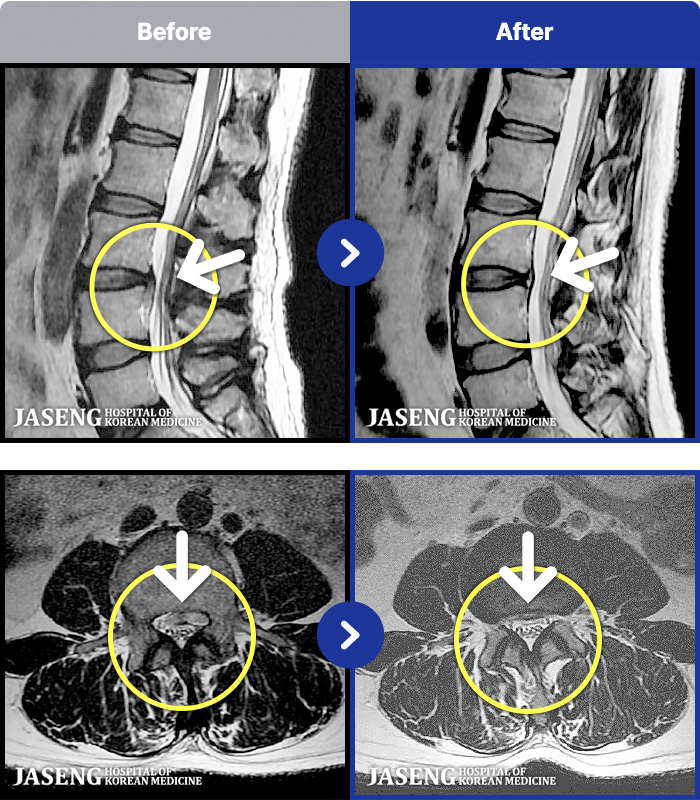

66 MRI ũ ʸ Ȯϼ.